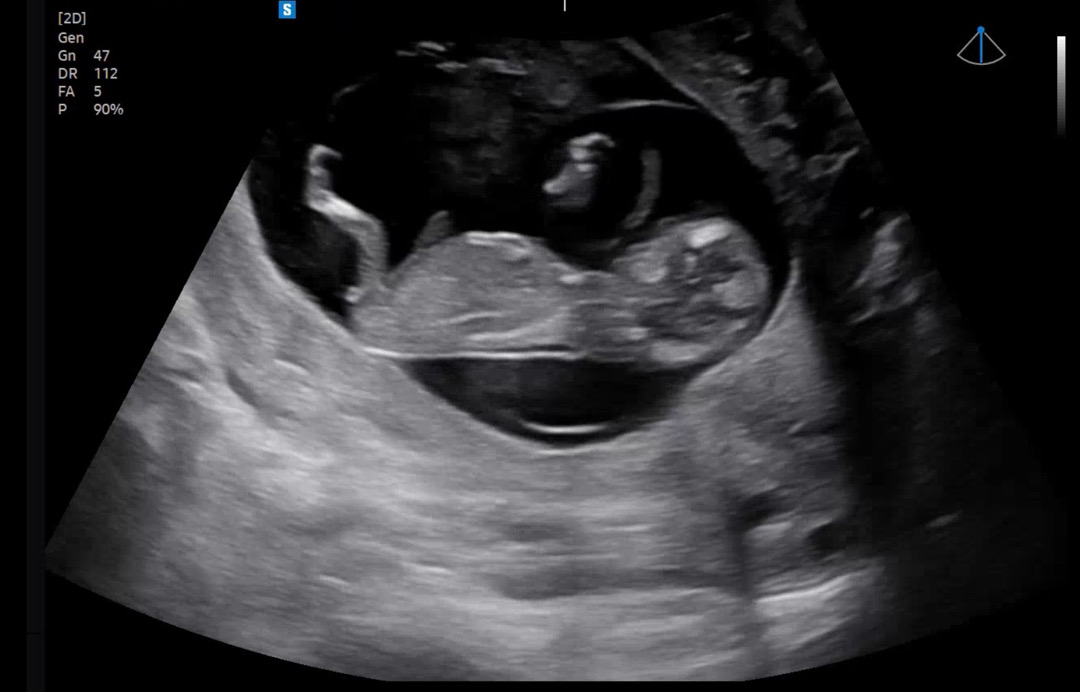

12주차 기형아검사하고 왔는데 각도법 궁금하네요! 제눈엔 평평해보이는 일자같은데 어떠세요?! :-) 고수님들 부탁드려요😊🙏🏻

확대해서보면 살짝위로 가있는듯 한게 아들인거같아요~ 초음파에 다리사이로 삼각점이 보이면 아들이에요!